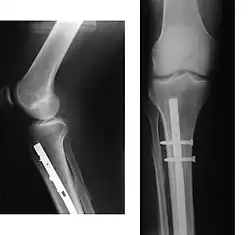

Internal and external views of an arm with a compound fracture, both before and after surgery

A bone fracture (abbreviated FRX or Fx, Fx, or #) is a medical condition in which there is a partial or complete break in the continuity of any bone in the body. In more severe cases, the bone may be broken into several fragments, known as a comminuted fracture.[1] An open fracture (or compound fracture) is a bone fracture where the broken bone breaks through the skin.[2]